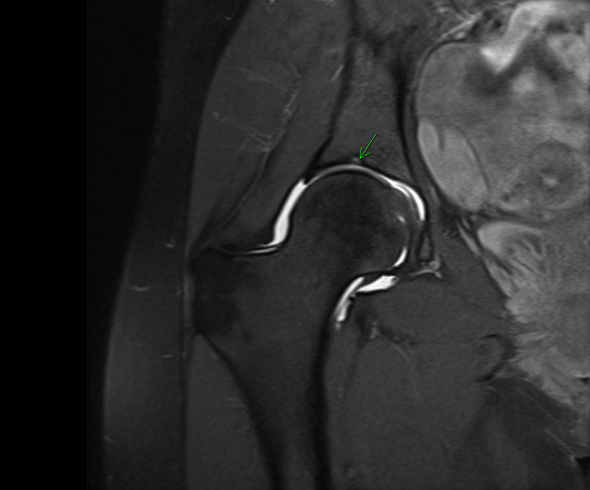

Рентгеновские снимки: Синовит тазобедренного сустава